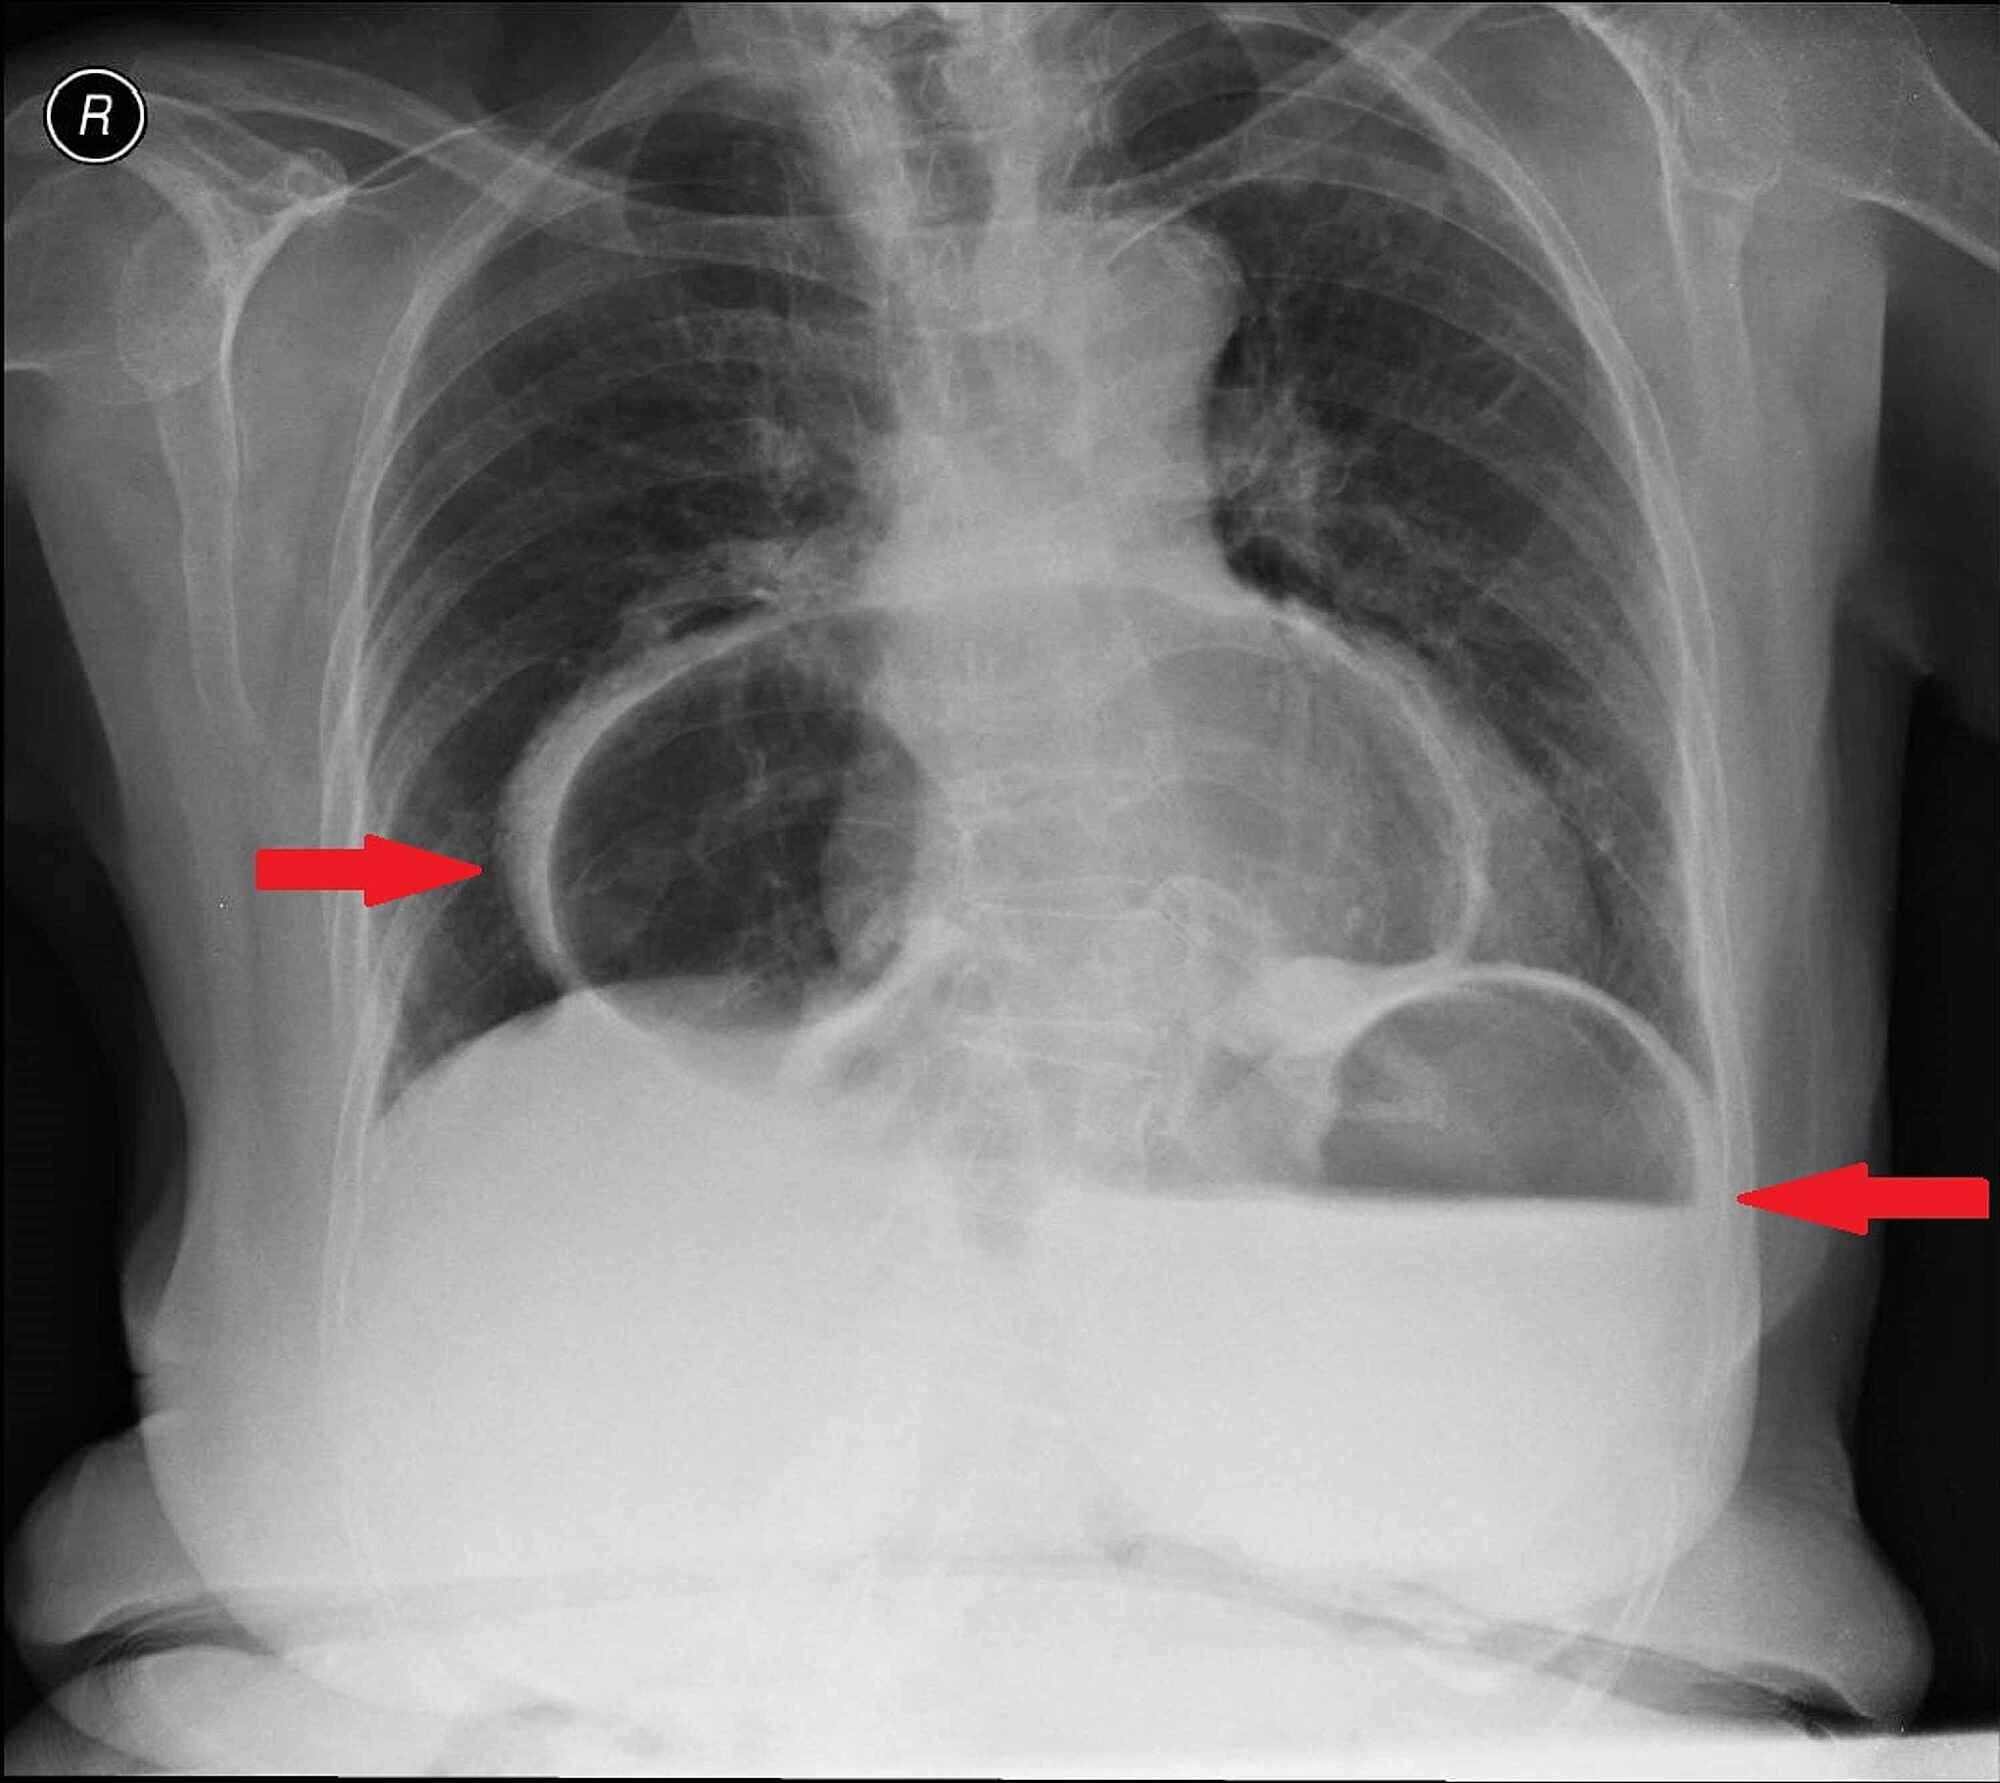

“A Large Hiatal Hernia” Atypical Presentation of Gastric Volvulus Gastric Volvulus Radiographics Gastric rotation and volvulus may occur in an organoaxial plane (along the long axis of the stomach) or in the mesenteroaxial plane. Gastric volvulus is a rare entity with a spectrum of acute and chronic clinical presentations. Gastric volvulus can be defined as an abnormal rotation of the stomach. It can be both an emergency and a chronic intermittent. Gastric. Gastric Volvulus Radiographics.